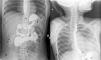

Biopsia de epiplón: adenocarcinoma pobremente diferenciado. A: tinción H/E 20x. Tejidos blandos infiltrados por neoplasia maligna de apariencia epitelial. B: tinción H/E 10x. Células de aspecto infiltrante poco cohesivas, alguna con morfología plasmocitoide, núcleo excéntrico desplazado por vacuolas intracitoplasmáticas. Imágenes cortesía de la Dra. María Cecilia Loredo (Departamento de patología, Nuevo Hospital Monte España).